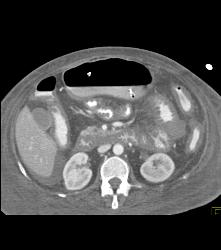

Wet Bowel Pattern and Low Flow State With Small Mesenteric Vessels- Celiac, SMA